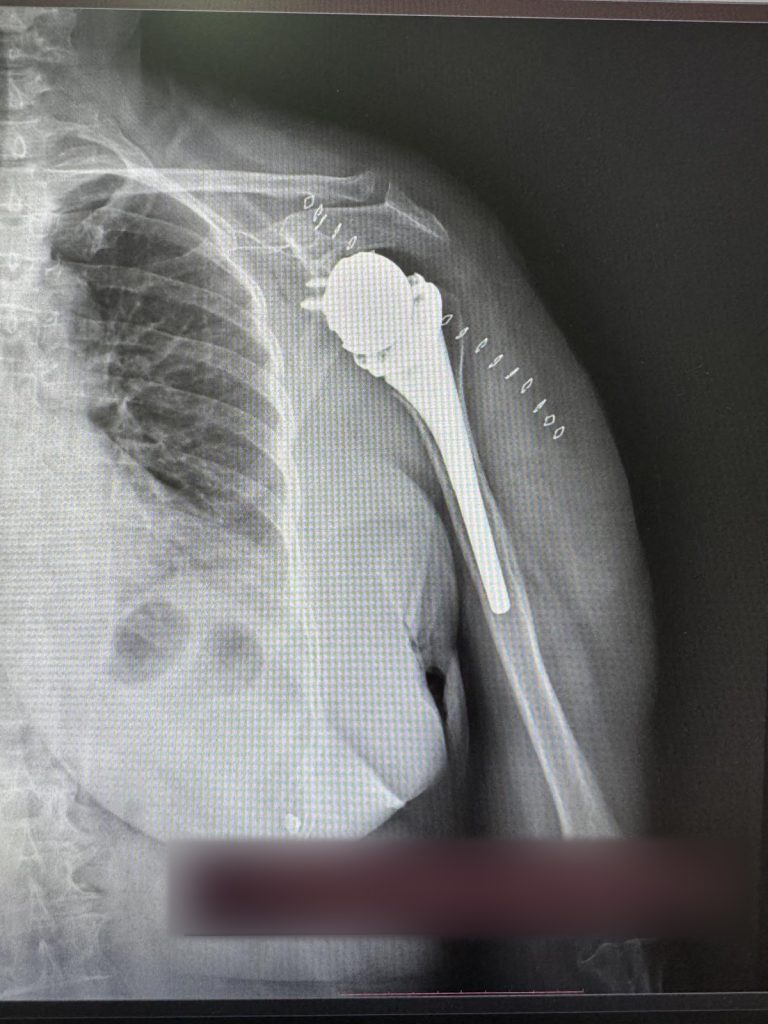

Për herë të parë në Klinikën e Ortopedisë të Qendrës Klinike dhe Universitare të Kosovës janë kryer dy operacione për vendosjen e protezave të supit.

ShSKUK ka njoftuar se ekipi mjekësor në përbërje të dy ortopedëve, si dhe ekipit nga Klinika e Anesteziologjisë dhe stafit infermieror, me sukses të plotë kanë kryer këto dy operacione ortopedike.

“QKUK kishte përfituar si donacion tavolinën operative për ndërhyrje në krahë, nga Klinika me renome botërore Schulthess Klinik, Zvicër”.